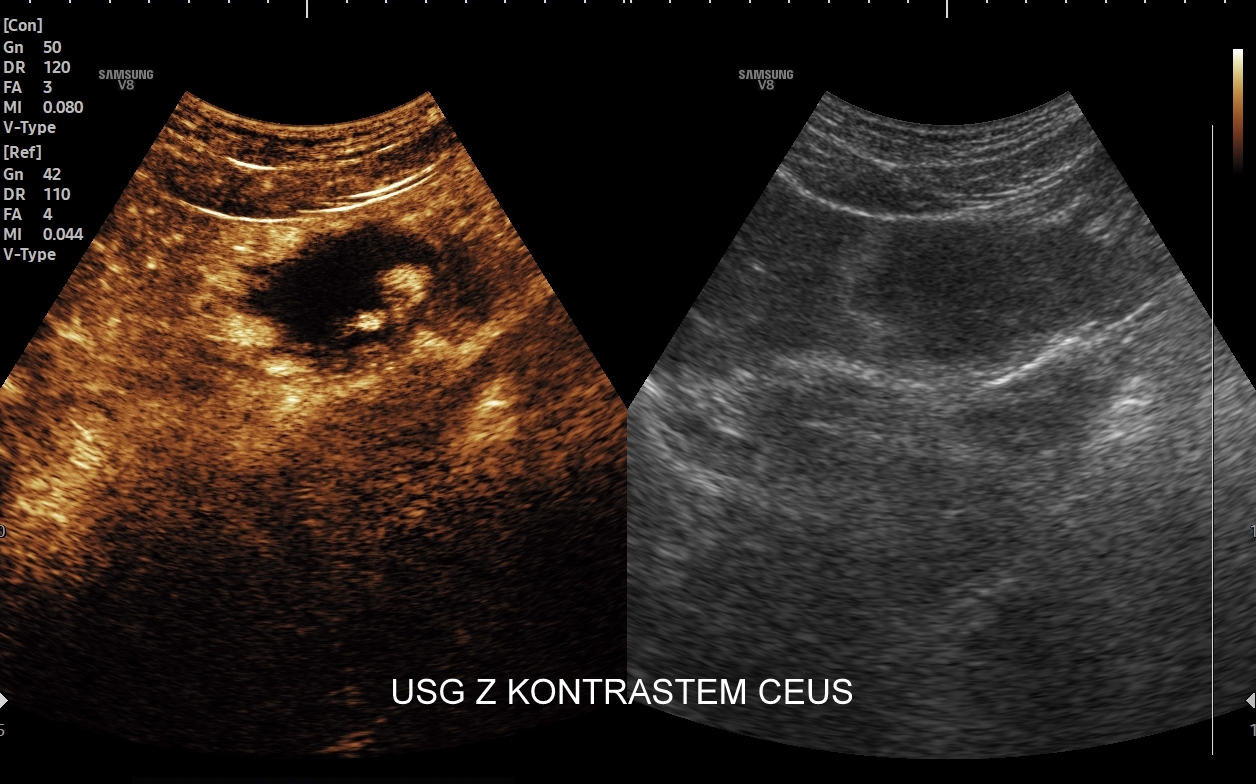

Badanie USG z kontrastem, nazywane również CEUS (ang. contrast enhenced ultrasound), jest nowoczesną metodą diagnostyczną wykorzystywaną w różnorodnych wskazaniach medycznych, w szczególności przy ocenie guzów i zmian ogniskowych narządów wewnętrznych takich jak wątroba, nerki, trzustka, drogi żółciowe, naczynia krwionośne, a także piersi i jądra. Badanie CEUS wykonają Państwo w Interdyscyplinarnej Pracowni Ultrasonograficznej prowadzonej przez dr Tomasza Szczepańskiego we Wrocławiu, pioniera ambulatoryjnych oraz szpitalnych zastosowań badań CEUS w Polsce.

Badanie USG z kontrastem, z języka angielskiego CEUS (contrast enhanced ultrasound), jest badaniem ultrasonograficznym, podczas którego, zwykle dożylnie, podaje się specjalny kontrast w celu uwidocznienia struktur narządowych oraz tkanek, które niewystarczająco wyraźnie są widoczne lub charakteryzowane w klasycznym badaniu USG, a nawet w innych badaniach obrazowych jak tomografia komputerowa (TK) czy rezonans magnetyczny (MRI).

Strukturę kontrastu do USG stanowią mikropęcherzyki o wielkości <10 μm zbudowane z osłonki lipidowej, w której zamknięty jest neutralny gaz heksafluorek siarki (SF6). Mikropęcherzyki po podaniu dożylnym przedostają się mikrokrążenia narządów i są w nich wykrywane za pomocą obrazowania USG specjalnie do tego przystosowanym aparatem. Oprócz dożylnego podawania kontrastu, w przypadku niektórych wskazań, może być on także administrowany dopęcherzowo.

Badanie USG z kontrastem najczęściej wykorzystuje się do oceny zmian ogniskowych w wątrobie, potocznie nazywanych guzami wątroby, z których wiele ma na tyle specyficzny obraz mikrounaczynienia w obrazowaniu CEUS, że możliwe jest uniknięcie konieczności badania obciążającymi metodami TK lub MRI. Badanie CEUS w przeważającej większości pozwala odpowiedzieć, czy zmiana ogniskowa wątroby ma cechy złośliwe czy łagodne. Dodatkowo CEUS jest pomocny do wykrywania przerzutów do wątroby pochodzących z nowotworów w innej lokalizacji. W przypadku przerzutów o wielkości mniejszej niż 1 cm CEUS ma większą czułość aniżeli badanie TK.

CEUS jest badaniem w czasie rzeczywistym pozostającym pod kontrolą operatora, podczas którego możliwe jest wykonanie próby czynnościowej oraz natychmiastowe powtórzenie całego badania w razie konieczności. Możliwości takich nie dają ani TK ani MRI. Dodatkowo CEUS cechuje się o wiele większą rozdzielczością czasową w porównaniu do wspomnianych metod, co umożliwia uwidocznienie wczesnej fazy tętniczej unaczynienia podejrzanej onkologicznie zmiany ogniskowej w wątrobie i jej lepszą charakterystykę.